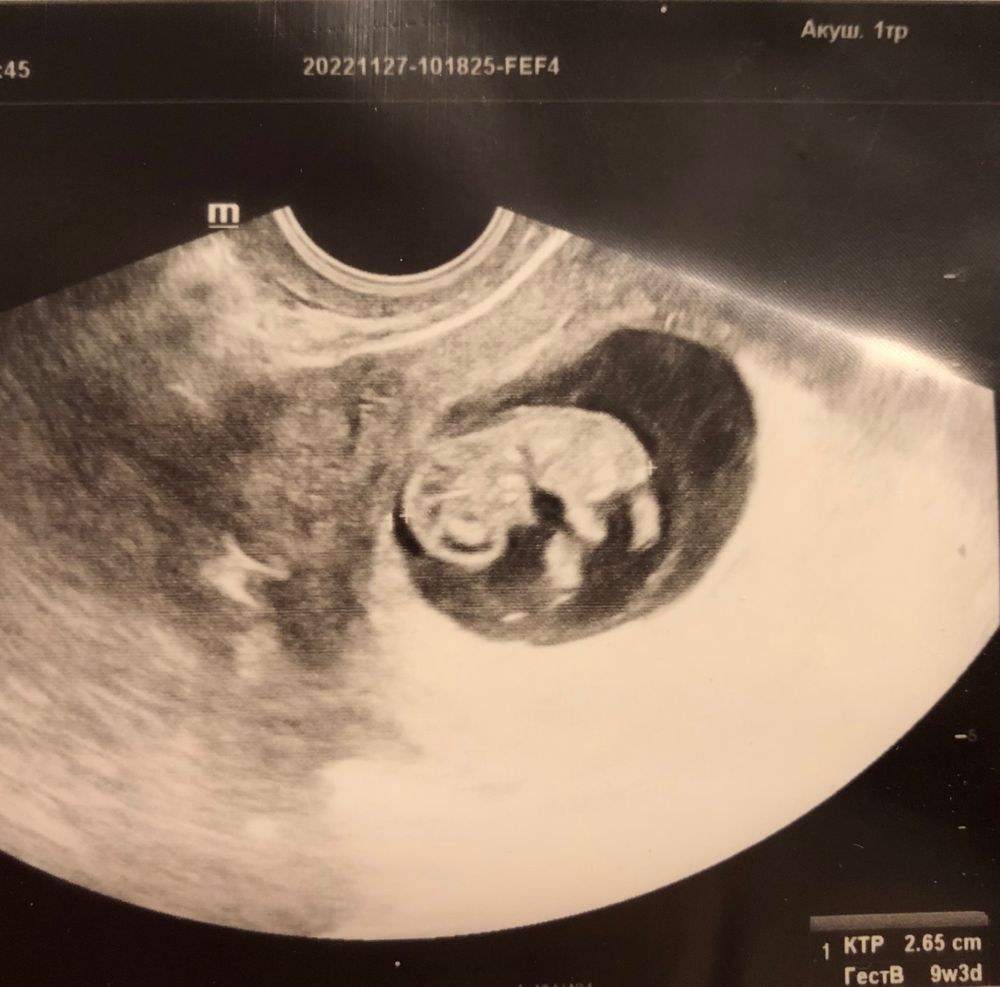

Креветка на месте 💙

Ровно в 9 недель сходила на узи 2й раз, тк стало тянуть низ живота. Проверить, что все хорошо.

Человек на месте, в порядке, дрых, судя по всему. Лёгкий тонус по передней стенке, так что я «в домике» 🙆🏼♀️. Магний и полежать. Зато теперь есть оправдание)))